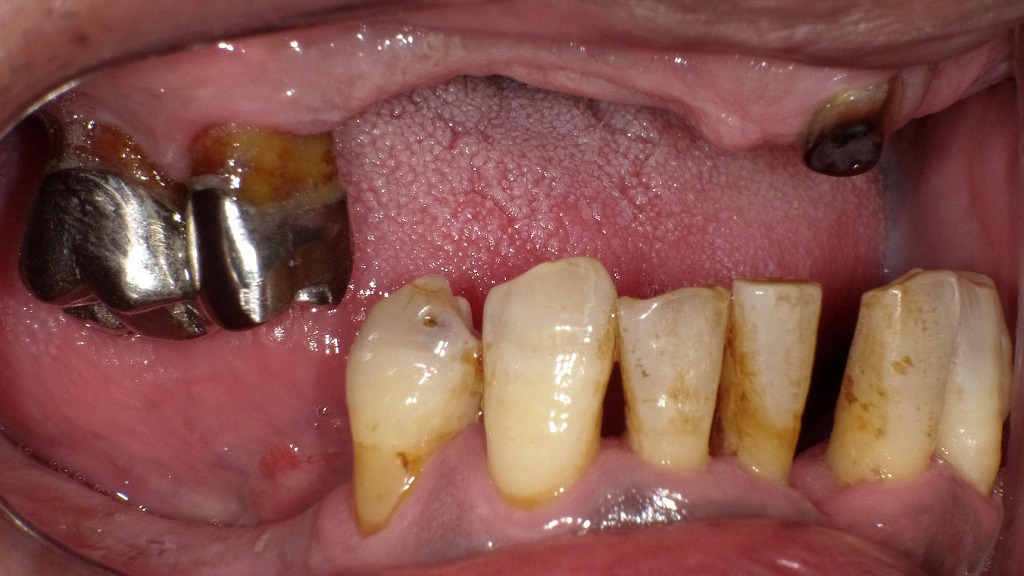

歯周病による歯ぐきの炎症や歯槽骨の破壊は、炎症性物質を通じて血糖値のコントロールを悪化させることが知られています。一方で、糖尿病があると免疫機能が低下し、歯周病が重症化しやすくなります。歯の動揺や歯肉退縮が見られる場合、歯周病治療と血糖管理を同時に行うことが、全身の健康を守るうえで重要です。

🦷糖質と口腔内の健康の関係

🍡柔らかい炭水化物に偏る理由

- 歯周病や虫歯があると、噛みにくい食品を避けがち

- 結果として、柔らかく糖質の多い食品に偏る

🧠口の健康は全身の健康に直結!

💡糖質制限と口腔ケアの連携が重要

- 口腔環境の悪化 → 食生活の偏り → 血糖コントロール悪化

- 食事と歯の健康は、互いに深く関わっている

実は「糖尿病」と「お口の健康」には深い関係があることをご存知ですか?糖尿病の方は歯周病が進行しやすく、逆に歯周病が血糖コントロールを悪化させることもあるため、定期的な歯科検診がとても重要です。

当院では、糖尿病とお口の健康の関係に注目し、歯周病の早期発見・治療に力を入れています。